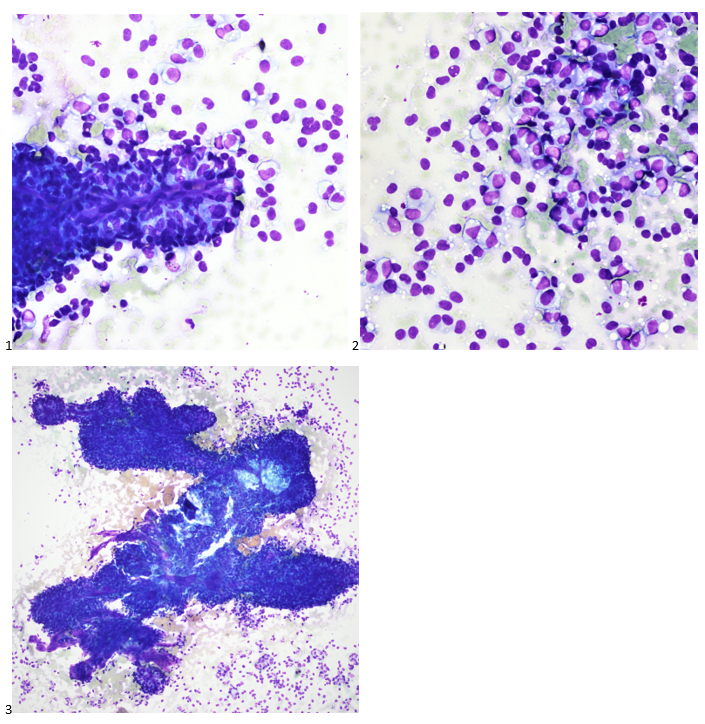

P.S. Sometimes diving and cytology overlap under the microscope, too!